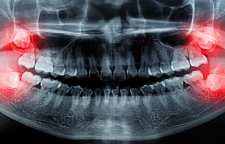

اصلاح طرح لبخند تصحیح عیوب خنده است و شامل مواردی از قبیل اصلاحات بر روی فاصله موجود در بین دندانها، رنگ از دست رفته ی دندان ها، دندانهای کوتاه و باریک، دندانهای کج، دندانهای پوسیده و لب پریده، لکههای دندان، کجی دندان، شکستگی و ترکخوردگی دندان، دندانهای افتاده یا کشیده شده، لبخند لثهای است.